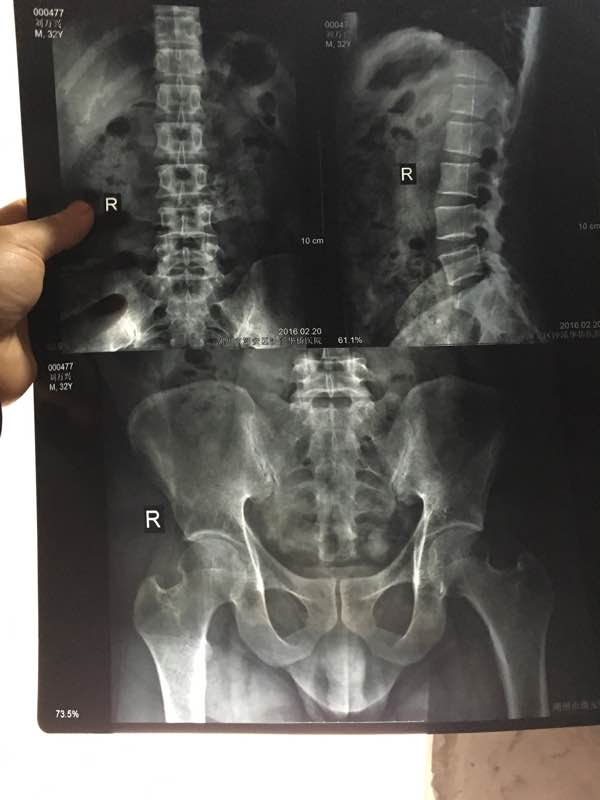

帮忙看看片

建议把诊断结果也发过来,